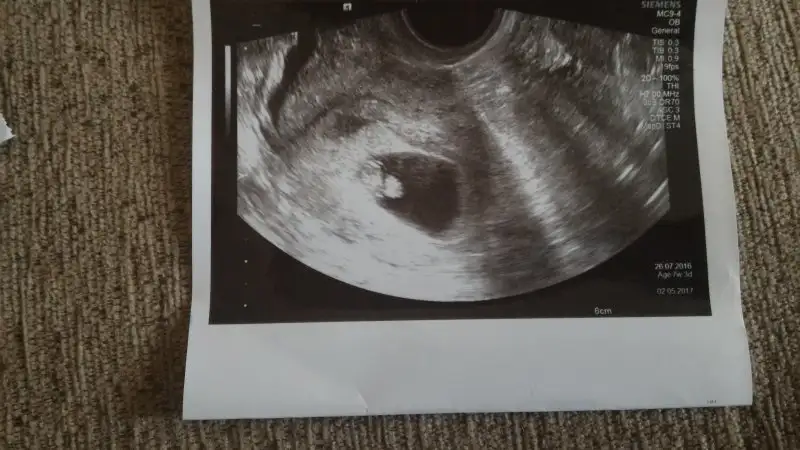

Merhabalar, bu başlığı birkaç haftadır takip ediyordum. Usg görüntümüzü paylaşmak için 8.haftamızı bekliyordum. Hamile olduğunu öğrenen her anne adayı gibi evvela sağlıklı ve hayırlı bir evlat olmasını niyaz ediyorum Rabbimden ama insan merak da ediyor tabii :))

Iki adet usg görüntüsü paylaşıyorum; birinde miniğimiz 6+1 diğerinde ise 8+0

Cinsiyet tahminlerinizi ve güzel dualarınızı heyecanla bekliyorum hanımlar, sevgiler ^.^

Ufak bir düzeltme: Sevgili @slvester, ben bu mesajı yanlışlıkla genital nub ile ilgili başlığa yazmış oldum ama sanırım haftamız itibariyle doğru yer burası ^.^

Siz ve diğer tüm arkadaşların tahminlerini merakla bekliyorum ^.^